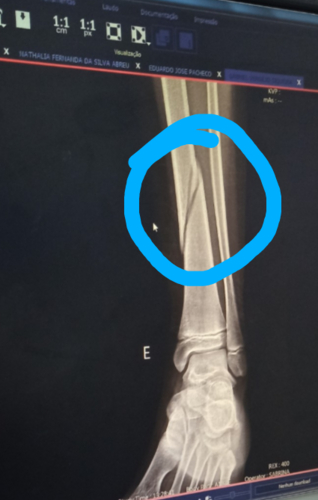

Gabriel estuda no 7° ano no colégio cívico militar Gottbier Muller , no dia 22/09 , uma professora não foi e a turma ficou com aula vaga, nisso liberaram as crianças pro pátio , sozinhos sem supervisão de um adulto, nisso, ele e mais duas crianças( um menino e uma menina) ficaram sentados , até que essa menina , pediu pra ele a acompanhá-la, nisso ela o abraça e começa a dar chutes em sua perna , meu filho ficou com a perna firme pra não sair , até que no terceiro ou quarto chute ele sai com muita dor , cai ajoelhado , e logo após começa a se bater de muita dor ( tipo tendo convulsões) …. Ai, só depois disso que uma professora viu e vai olhar o que estava acontecendo….. um outro menininho da turma resolveu ir chamar meu filho mais velho que também estuda no mesmo colégio, e só depois que foram atrás de monitor, pedagoga , enfim dos responsáveis. Um dos monitores militares, resolve massagear o tornozelo, pois achou que ele tinha torcido o pé , e só depois que acionaram o siate e me ligaram. O siate nós atendeu, e o encaminhou para o hospital do trabalhador, lá foi feito raio-x e mostrou que ele quebrou a tíbia em dois lugares. No dia 03/10 tive retorno médico, o dr° pediu repouso absoluto, pra tentar calcificar, mas que tudo indica que terá que operar…. Meu filho tem 11 anos e por essa situação está tendo que usar fraldas, banho só de paninho.…. Estou tento muitos gastos , e nem o colégio , nem a família da menina está me ajudando…. Sou autônoma, se não trabalho não ganho, e quase não estou conseguindo trabalhar , por isso que resolvi fazer essa vaguinha,pra que eu possa pagar as contas da casa, manter os cuidados com ele .